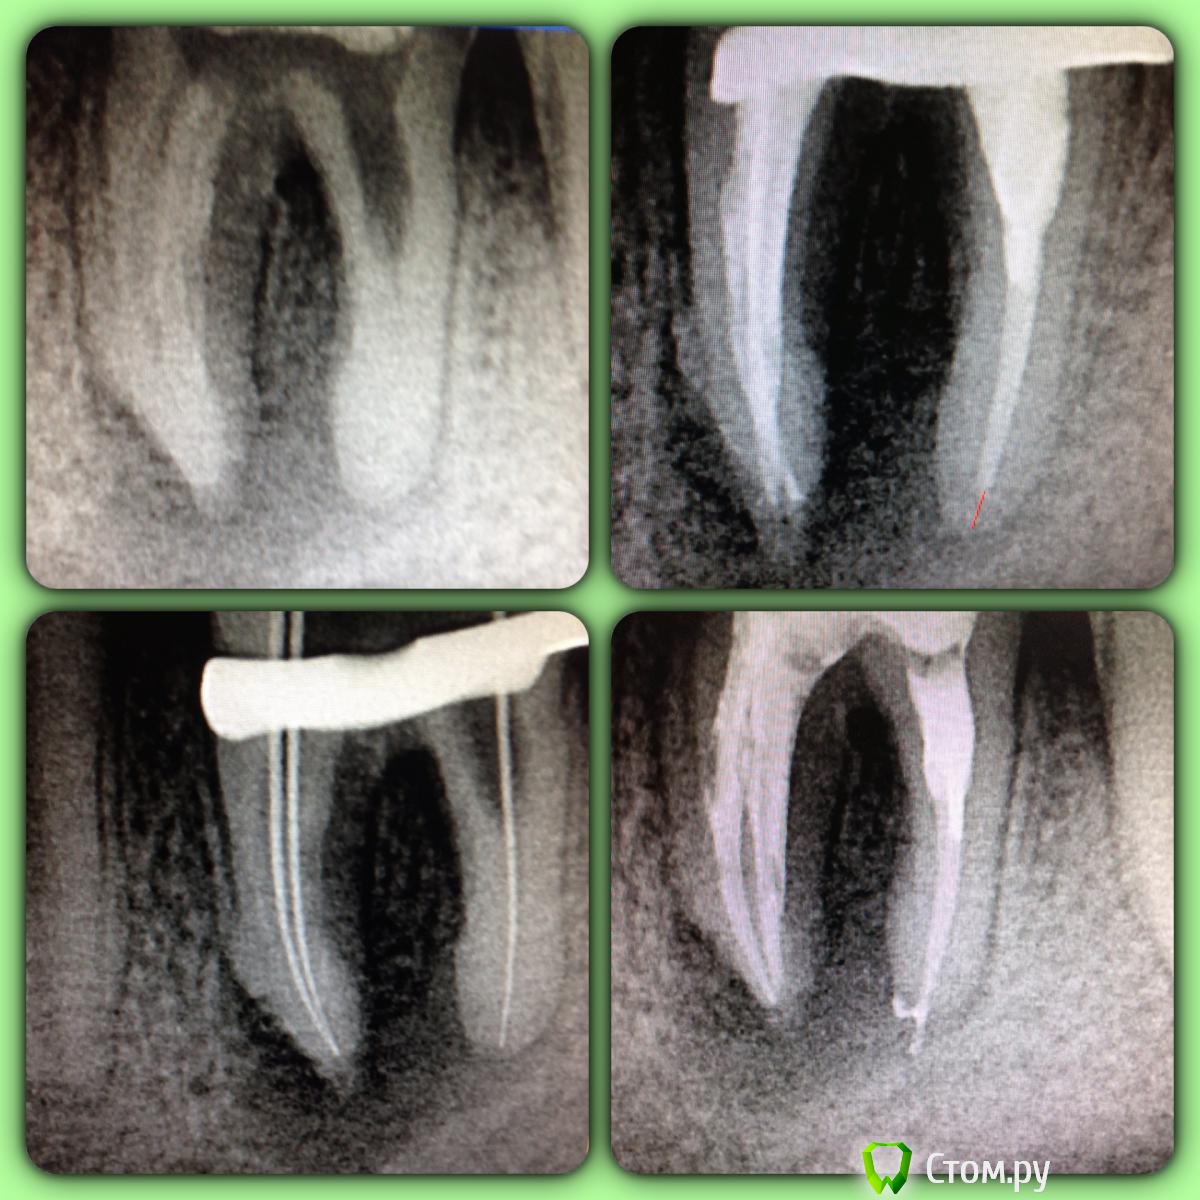

SSTi Опубликовано 9 июня, 2014 Автор Поделиться Опубликовано 9 июня, 2014 Продолжение истории сообщения 87. После кальция в каналах чисто. Первый раз недолет небольшой в дистальном. Решил перепломбировать его и снова плевок силером за апекс. ... Не так критично, как мне кажется, как поры. Поэтому думаю переделать. Хотя с таким количеством ступеней в медиальных и разбитым дистальным думал будет хуже. ... Прихожу к мнению , что хочу вертикалку))) 1 Ссылка на комментарий

SSTi Опубликовано 10 июня, 2014 Автор Поделиться Опубликовано 10 июня, 2014 32 зуб. На верхушке большое разрежение. Холодовой тест показал, что 31 жив, 32 погиб смертью храбрых, 33 жив. С язычной стороны свищ. В первое посещение открылись, помылись , канал для нижней двойки широкий очень. Обработка до ф2 , упор 40.02. Кальций. Во второй визит- вымываем кальций, пломбируем. Свищ закрылся. Клык пока не трогал. Ссылка на комментарий

SSTi Опубликовано 10 июня, 2014 Автор Поделиться Опубликовано 10 июня, 2014 Кармана нет, снова делал больше контраст. С вестибулярки не так плохо. Язычно тоже. Подвижности нет. Ссылка на комментарий